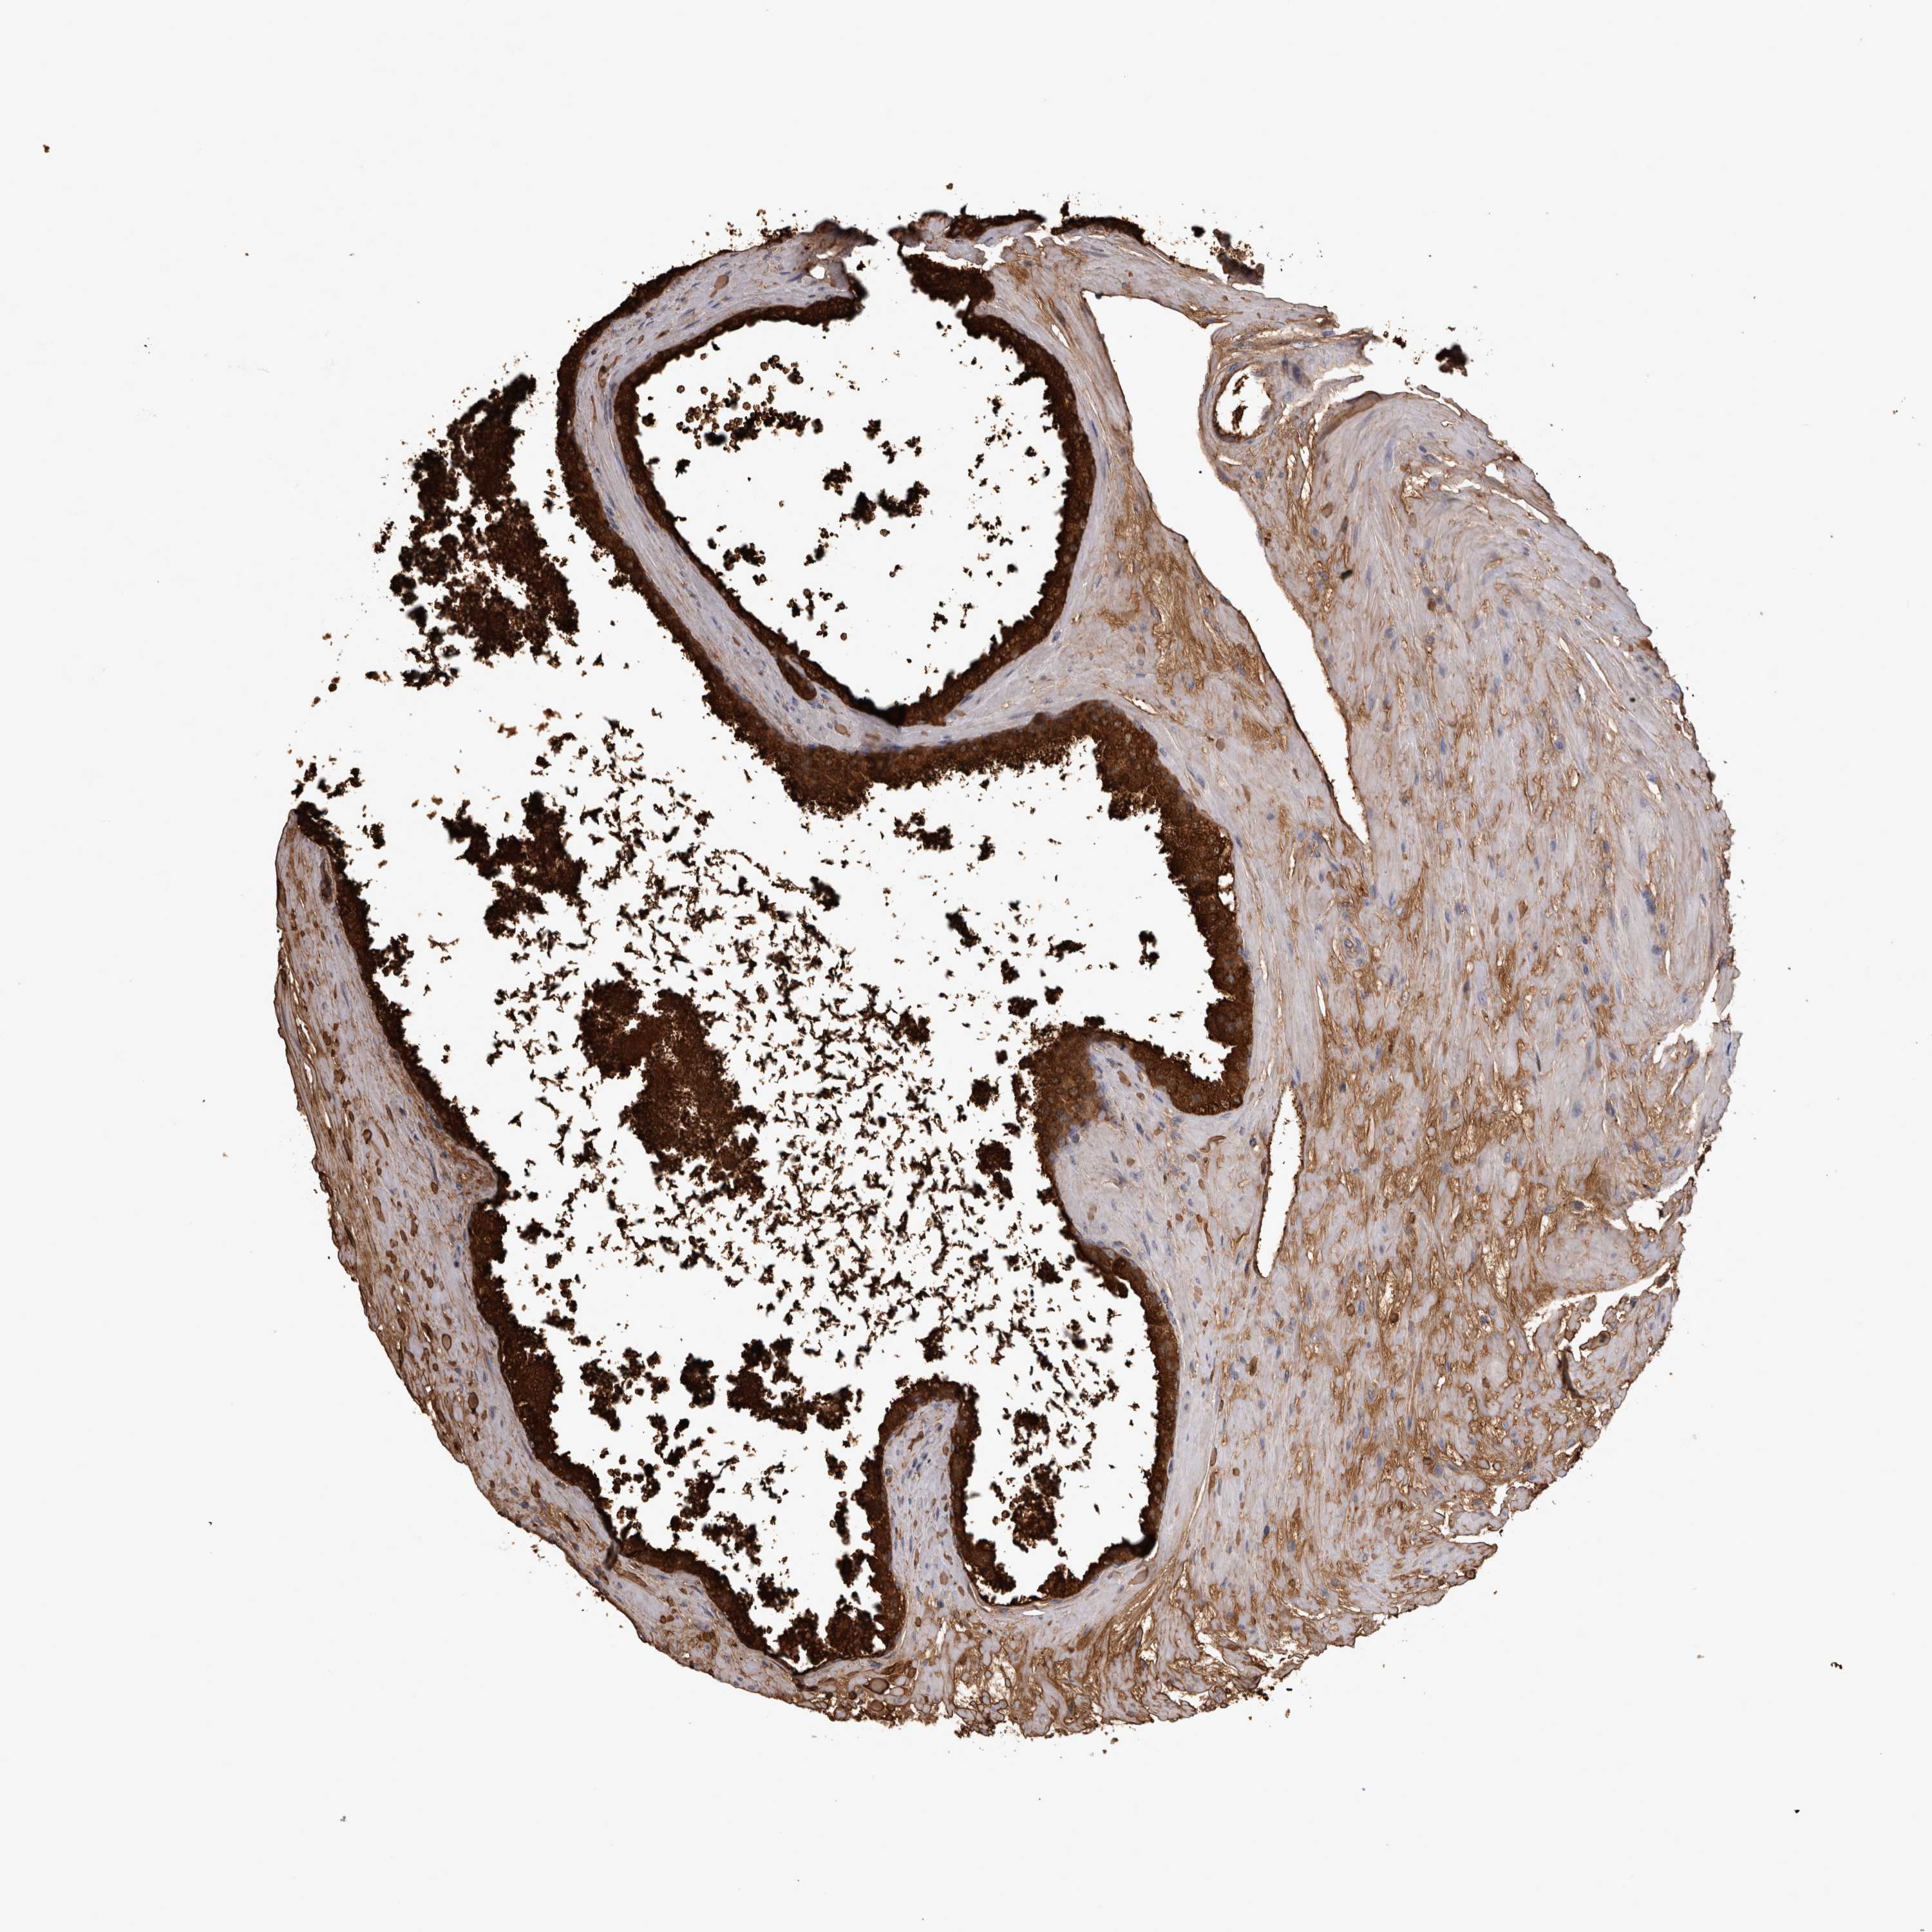

PROSTATE CANCER - Protein expressioni

A mouse-over function shows sample information and annotation data. Click on an image to view it in a full screen mode. Samples can be filtered based on level of antibody staining by selecting one or several of the following categories: high, medium, low and not detected. The assay and annotation is described here.

Antibody stainingi

Antibody staining in the annotated cell types in the current human tissue is reported as not detected, low, medium, or high, based on conventional immunohistochemistry profiling in selected tissues. This score is based on the combination of the staining intensity and fraction of stained cells.

Each image is clickable and will lead to virtual microscopy that enables deeper exploration of all samples and also displays staining intensity scores, fraction scores and subcellular localization as well as patient and tissue information for each sample.

Antibody HPA051257

Antibody CAB026357

Staining

High

Medium

Low

Not detected

Intensity

Strong

Moderate

Weak

Negative

Quantity

>75%

75%-25%

<25%

None

Location

Nuclear

Cytoplasmic/membranous

Cytoplasmic/membranous,nuclear

Adenocarcinoma, High grade

Adenocarcinoma, Medium grade

Adenocarcinoma, Low grade